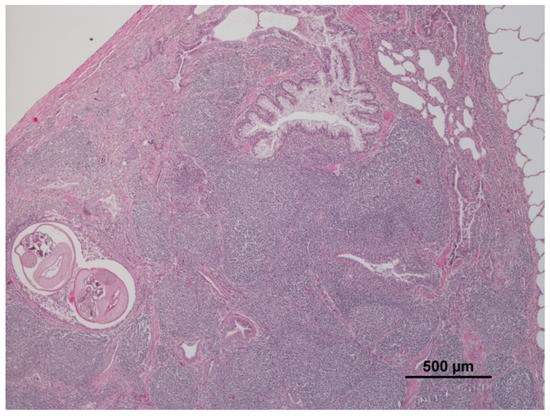

3.1. Lung

| Verminous bronchitis | 25 | 34.7 | panlobular | 8 | 11.1 | Renal steatosis | 2 | 2.8 |

| Lymphoid hyperplasia | 26 | 36.1 | Cellular changes: cell swelling; hydropic change; vacuolar change | 24 | 33.3 | Non-purulent nephritis | 16 | 22.2 |